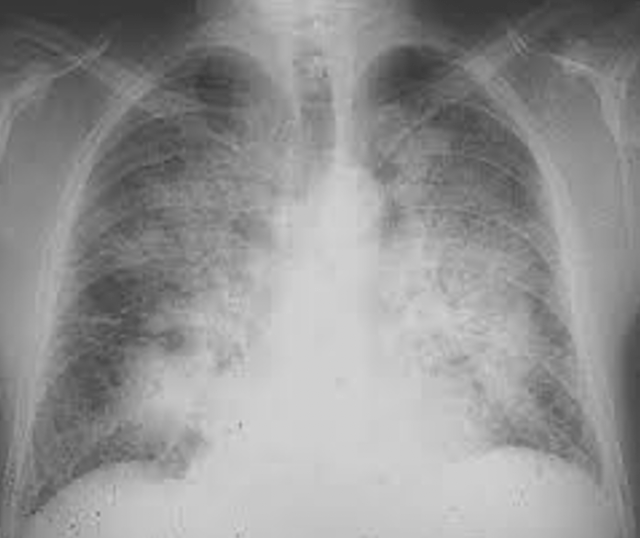

W ARDS, patologii leżącej u podstaw COVID-19, narządem dotkniętym chorobą są płuca, co skutkuje obrazowaniem:

Abnormalny skan tomografii komputerowej.

OSTRZEŻENIE, te ilustracje nie są specyficzne dla COVID-19! Widzimy je w przypadkach pneumopatii naciekowej, w tym ostrej hipoksemicznej śródmiąższowej pneumopatii, która może być obecna przy krwotokach wewnątrz pęcherzyków płucnych, pneumopatiach polekowych (amiodaron), toksycznych pneumopatiach i chorobach układu, a także przy zapaleniu naczyń. Należą one do grupy patologii płuc zgrupowanych pod ogólnym terminem ARDS.

Zmiany wyglądające jak zamarznięta, matowa szyba są typowe dla ARDS, a nie dla jakiejś szczególnej przyczyny.

Występują one w szczególności w zakaźnym zapaleniu płuc z tak zwanymi atypowymi zarazkami, takimi jak Mycoplasma Pneumoniae, Chlamydia Pneumoniae czy Legionella Pneumophila, ale także w niezakaźnych pneumopatiach.